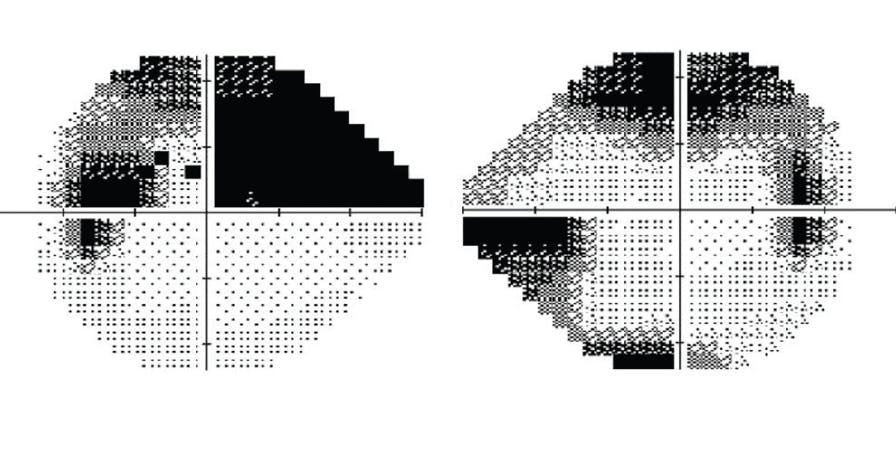

The optic nerve of the right eye exhibits superior and inferior thinning, and the optic nerve of the left eye exhibits marked inferior thinning. The optic disc hemorrhage observed by the referring ophthalmologist has resolved (Figure 2). OCT with ganglion cell analysis shows global thinning of the retinal nerve fiber layer (RNFL) that is consistent with high myopia. It also finds focal superior and inferior RNFL thinning in the right eye and inferior RNFL thinning in the left eye consistent with an examination of the optic nerves (Figure 3). Visual field testing demonstrates advanced loss in each eye that splits fixation only in the left eye (Figure 4).

Figure 4. Visual field testing shows advanced loss in each eye that splits fixation only in the left eye.